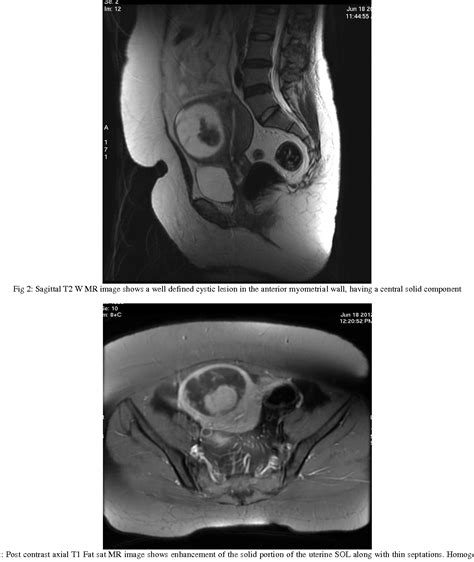

Diagnosing uterine myoma degeneration involves a combination of medical history, physical examination, and imaging tests. The diagnostic process typically includes:

• Imaging Tests: Ultrasound, MRI, or CT scans to visualize the fibroids and assess the extent of degeneration.